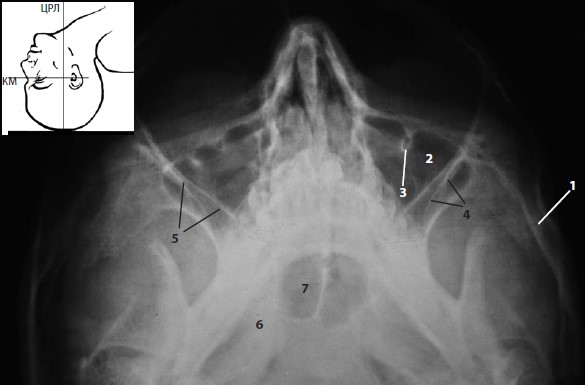

г -базальная (аксиальная, субментовертексная) проекция,

- базальная (аксиальная, субментовертексная) проекция. Под плечи лежащего на спине пациента подкладывают валик с таким расчетом, чтобы закинутая назад голова касалась кассеты теменем, а инфраорбитомеатальная линия (ИМ) была параллельна кассете и перпендикулярна центральному рентгеновскому лучу.

Базальная (субментовертексная) |

Клиновидная пазуха и решетчатый лабиринт |

Перелом |

Латеральная стенка орбиты |

Перелом латеральной стенки орбиты |

Скуловая дуга |

Перелом скуловой дуги |